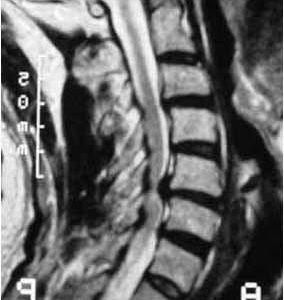

Die Spinalkanalstenose - Einengung des Wirbelkanals an der Halswirbelsäule

Bei einer Spinalkanalstenose an der Halswirbelsäule ist der Wirbelkanal – also der Raum, durch den das Rückenmark verläuft – verengt. Diese Einengung kann Druck auf das Rückenmark ausüben. Wenn dadurch die Funktion des Rückenmarks gestört ist, spricht man von einer Myelopathie. Typische Beschwerden können Kribbeln, Schwäche oder Unsicherheit in Armen und Beinen, Gangstörungen oder feinmotorische Probleme (z. B. beim Schreiben oder Knöpfen) sein. In fortgeschrittenen Fällen kann es auch zu Problemen mit der Blasen- oder Darmkontrolle kommen. In leichten Fällen kann eine Behandlung mit Physiotherapie erfolgen, in fortgeschrittenen Fällenist meistens eine Operation nötig, um den Druck vom Rückenmark zu nehmen.

Der Bandscheibenvorfall an der Halswirbelsäule

Ein Bandscheibenvorfall an der Halswirbelsäule begünstigen Fehlhaltungen im Alltag, z. B. langes Arbeiten mit gesenktem Kopf, was den Druck auf die Bandscheiben erhöht und zu deren Austrocknung und Elastizitätsverlust führt. Es gibt zwei Hauptformen: seitliche Vorfälle mit Nervenwurzelreizung (ausstrahlende Schmerzen bis in die Finger) und mittige Vorfälle mit möglichem Druck auf das Rückenmark, was schwerwiegendere Folgen wie Gangunsicherheit oder Lähmungen haben kann. Die Diagnose erfolgt durch Anamnese, körperliche Untersuchung und meist MRT. Die Behandlung beginnt in der Regel konservativ mit Schmerzmitteln, Physiotherapie und ggf. Injektionen (PRT). Eine Operation erfolgt, wenn konservative Maßnahmen nicht erfolgreich waren oder neurologische Störungen bestehen. Bei Operationen entscheidet die Lage des Vorfalls über den Zugang (von vorne oder hinten) und die Wahl zwischen Bandscheibenprothese oder Versteifung mittels Cage. Der Zugang von hinten kann endoskopisch erfolgen und eignet sich für seitliche Vorfälle, der Zugang von vorn für mittige Vorfälle.